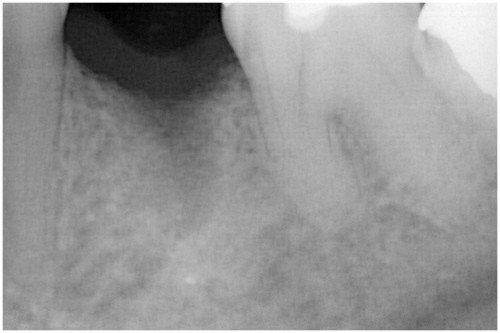

根の先に病巣ができています。

かぶせ物と土台を外します→根の管に詰まっている薬を外します→再び根の管を拡げます

根の管を拡げ終えました→症状がなくなりました→最終的なお薬を詰めます

土台の型を取ります→土台を付けます

歯の周りを削ります→被せ物を付けます